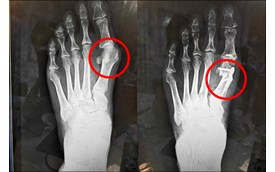

61歲的看護大哥因為痛得睡不好、走路像企鵝,跛著腳走進診間。X光檢查顯示,他的關